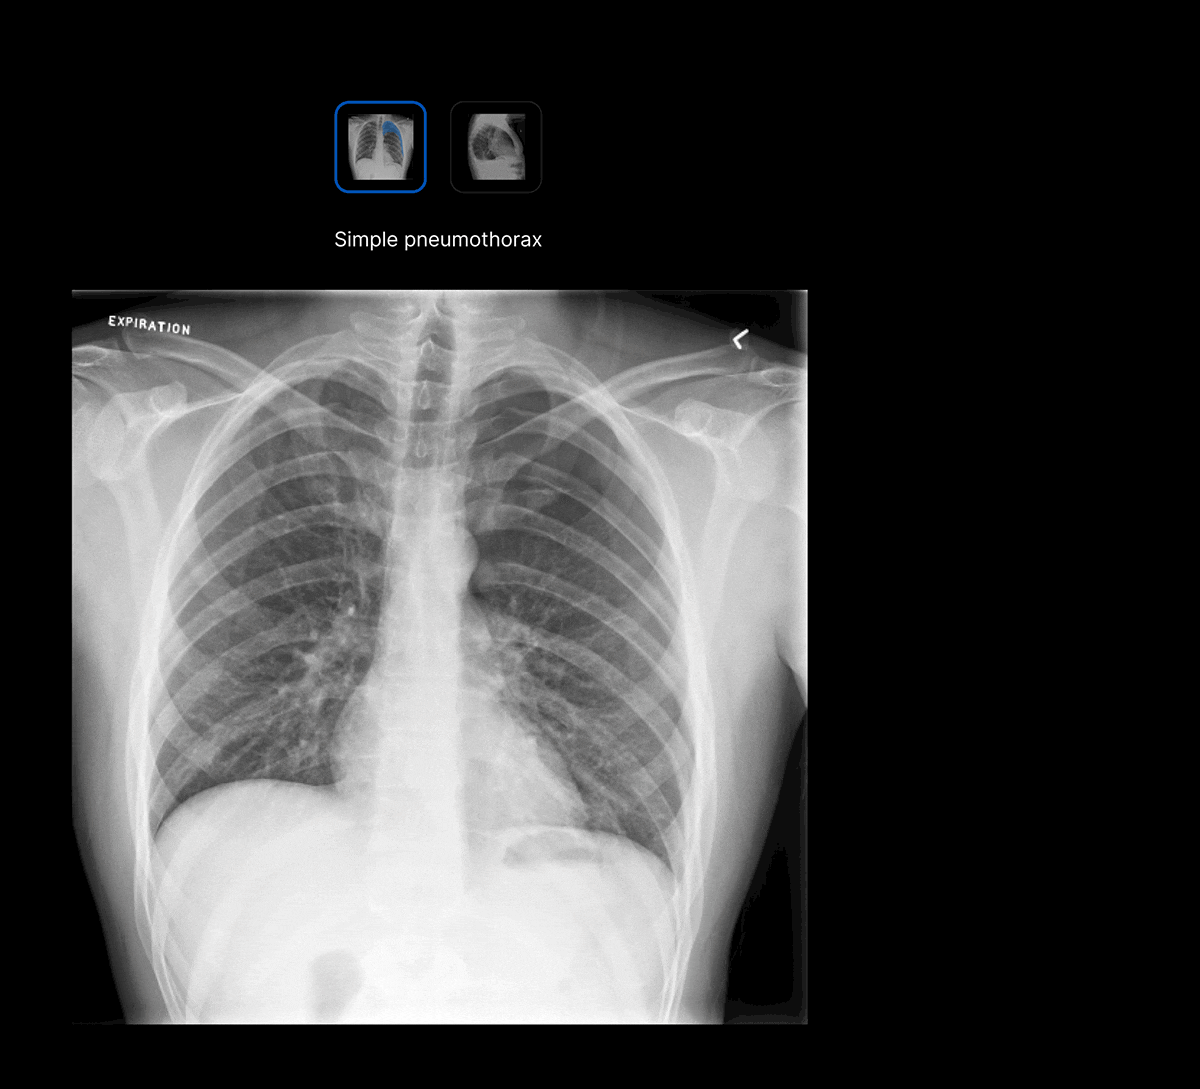

Harrison.ai chest X-ray (CXR) is a comprehensive AI solution for chest X-rays that detects up to 124 findings in under 20 seconds, boosting emergent and incidental capture while surfacing urgent cases for review first – all within the workflow you’re used to.

Intuitive UI. Powerful AI.

Designed by radiologists.

Designed to reduce cognitive load.

Seamless workflow.

The UI integrates seamlessly with PACS/ RIS, displaying a resizable, no-click overlay window with findings and localisation.